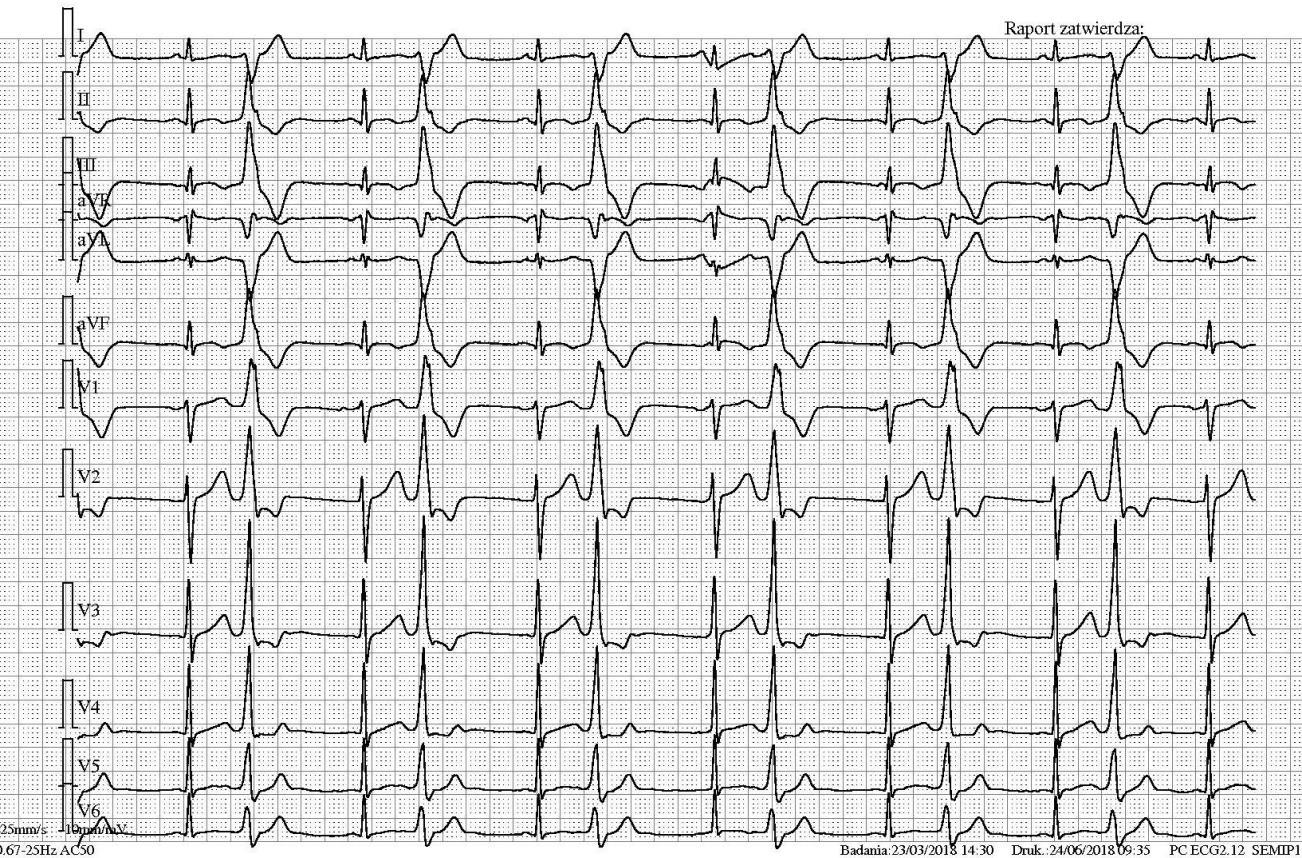

Na ekg poniżej (przesuw 25 mm/s) stwierdza się:

50-letni pacjent zgłasza uczucie niemiarowej czynności serca. EKG (przesuw 25 mm/s) poniżej. W postępowaniu należy uwzględnić:

75-letni mężczyzna zmierzył sobie w domu samodzielnie ciśnienie tętnicze automatycznym aparatem. Urządzenie pokazało puls 41/min. Pacjent wezwał zespół ratownictwa medycznego, który wykonał ekg (przesuw 25 mm/s) jak poniżej. Przyczyną stwierdzonego wolnego pulsu jest:

W zapisie ekg 80-letniego mężczyzny (przesuw 25 mm/s) stwierdza się:

U 60-letniego mężczyzny z cukrzycą, zwężoną prawą tętnicą szyjną wystąpił niedowład prawostronny. EKG 25 mm/s jak poniżej. Wskaż fałszywe stwierdzenie:

80-letni pacjent krótkotrwale utracił świadomość podczas oddawania moczu. EKG jak na rycinie. Najbardziej prawdopodobną przyczyną utraty przytomności jest:

Jaka jama serca jest stymulowana?

20-letni mężczyzna do tej pory zdrowy, na nic się nieleczący miał kołatanie serca, które obecnie ustąpiło. Aktualne EKG poniżej. Należy rozpoznać: